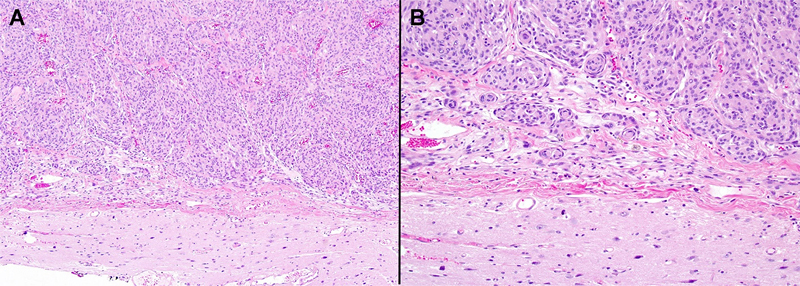

Figure 2. A, B. Most meningiomas with attached CNS parenchyma can be clearly interpreted as being non-invasive, given the broad, linear interface and clear leptomeningeal layer between the tumor and adjacent brain parenchyma.